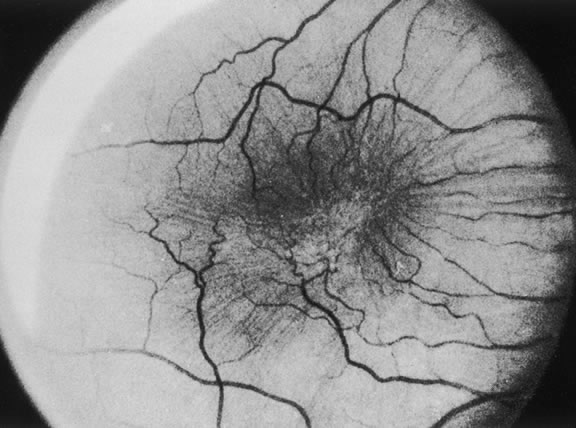

When the vitreous detaches from the area of the optic nerve head, a tag of tissue may be avulsed, and at times a complete ring of peripapillary tissue may come forward with the vitreous. The presence of this ring is pathognomonic for a PVD (Fig. 8). Electron microscopic studies on autopsy eyes with PVDs demonstrate frequent glial epipapillary membranes on the vitreous side of the ILM of the optic nerve and surrounding retina.70,71 There are interruptions in the epipapillary membranes, as well as separations of the membranes from the underlying ILM of the disc, both of which contained incarcerated collagen fibers identical with vitreous fibrils. This intimate association of the vitreous in the disc area accounts for the frequent avulsion of tissue in a PVD. Glial tissue occurs on the posterior hyaloid in 57% of PVDs.

Fig. 8. Gross pathology specimen of an eye of an 85-year-old patient with a posterior vitreous detachment. An epipapillary membrane has been avulsed and is suspended in the posterior hyaloid. The inset shows details of the epipapillary ring. (Foss RY: Anatomic and pathologic aspects of the vitreous body. Trans Am Acad Ophthalmol Otolaryngol 1973;77:171)